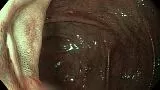

Пациент К.,60 лет, направлен на плановую колоноскопию с жалобами на длительную диарею и боли в правой подвздошной области, в анализах повышенный фекальный кальпротектин. На колоноскопии обнаружена одиночная язва у входа в илеоцекальный клапан , неправильной формы, с глубоким дном, на дне белый детрит, вокруг выраженные воспалительные явления, вокруг поверхностный рисунок при осмотре изменен, нерегулярный, взята биопсия. Илеоцекальный клапан не проходим для колоноскопа. На гистологии- язвенный дефект с дисплазией высокой степени, Болезнь Крона.

Колоноскоп- Olympus HQ-190. Осмотр  в режимах NBI  и  Near Focus.